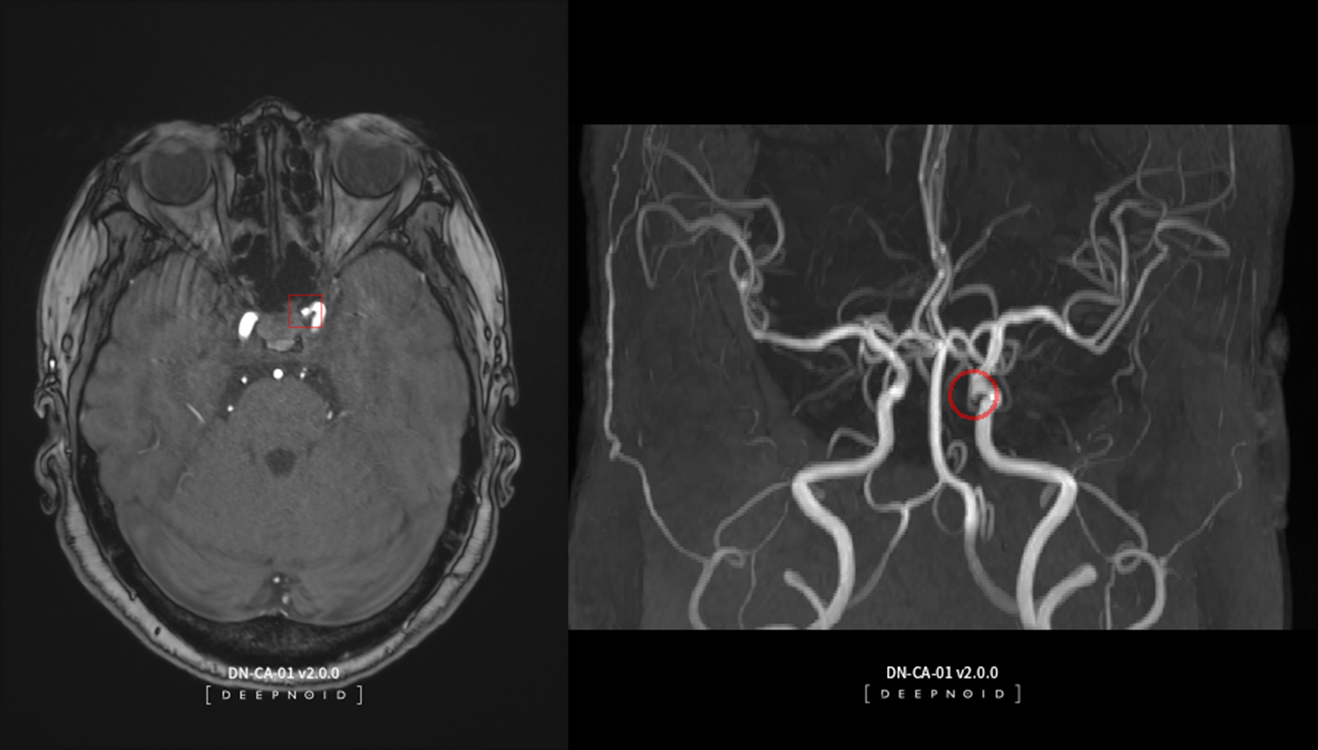

의료 인공지능(AI) 전문기업 딥노이드(대표이사 최우식, www.deepnoid.com)의 뇌동맥류 뇌영상검출·진단보조소프트웨어 '딥뉴로(이하, DEEP:NEURO)가 혁신의료기술로 선정됐다고 17일 밝혔다.

DEEP:NEURO는 뇌동맥류 의심 환자의 뇌혈관 자기공명혈관조영술(이하 MRA) 영상에서 뇌동맥류 의심 부위를 인공지능(AI)로 판독 및 분석하여 의료인의 진단을 보조하는 제품이다. 의료진들은 뇌혈관 MRA 내 뇌동맥류 결과 확인 시, DEEP:NEURO를 의료현장에서 판독보조용으로 사용 가능하다. 이에 영상판독 편의성과 정확도를 높임으로써 의료진의 빠른 대응과 치료가 필요한 뇌혈관질환의 골든타임을 지킬 수 있을 것으로 전망한다.